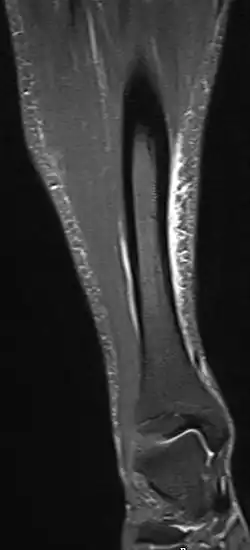

Magnetic resonance image of the lower leg in the coronal plane showing high signal (bright) areas around the tibia as signs of shin splints.

Shin splints are generally diagnosed from a history and physical examination.[3] The important factors on history are the location of pain, what triggers the pain, and the absence of cramping or numbness.[3]

Other potential causes include stress fractures, compartment syndrome, nerve entrapment, and popliteal artery entrapment syndrome.[19] If the cause is unclear, medical imaging such as a bone scan or magnetic resonance imaging (MRI) may be performed.[3] Bone scans and MRI can differentiate between stress fractures and shin splints.[13]